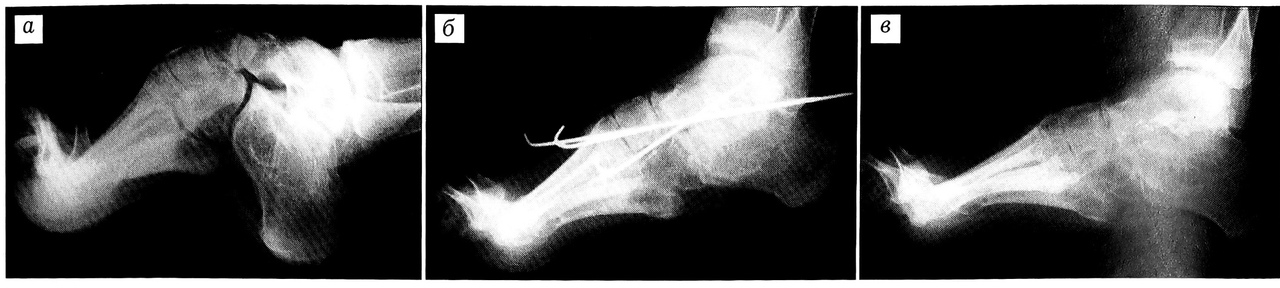

Больной К., 23 лет, диагноз: болезнь Фридрейха, эквино-экскавато-варусная деформация стоп, больше справа. 15.05.96 произведена операция: клиновидная резекция и трехсуставной артродез правой стопы с рассечением подошвенного апоневроза и фиксацией спицами. В послеоперационном периоде фиксация гипсовой лонгетой. Через 3 нед спицы удалены, наложен гипсовый сапожок с каблуком на 3 мес. В последующем больной пользовался ортопедической обувью. Контрольное обследование через 3 года: жалоб нет, форма стопы исправлена, анкилоз суставов состоялся (рис. 2). Исход лечения расценен как хороший.

Рис. 2. Рентгенограммы правой стопы больного К. 23 лет. Диагноз: эквино-экскавато-варусная деформация стоп на почве болезни Фридрейха. a — до операции; б — непосредственно после операции; в — через 3 года.